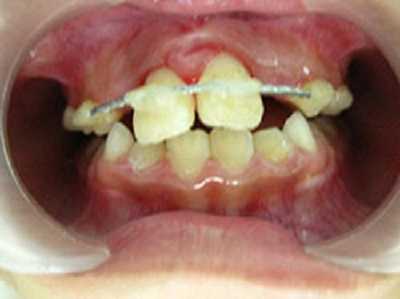

Răng bé khi chưa được nắn chỉnh đúng phương pháp.

Mẹ bé cho biết cách đây gần 1 tháng, người nhà thấy 2 răng cửa hàm trên mới mọc của bé bị thưa kẽ nên dẫn bé đến phòng nha tư gần nhà để chỉnh răng. Tại đây, bé được choàng  thun vào cổ răng của 2 răng cửa để kéo khít khe hở. Được gần 2 tuần, khe hở có giảm nhưng bé không ăn nhai được, răng đau nhức dữ dội, nướu răng sưng đỏ, sờ chạm dễ chảy máu. Mẹ bé than “đẹp đâu không thấy chỉ thấy răng con tôi đau nhức và sắp rụng”.

Khám lâm sàng cho thấy: gai nướu răng cửa hàm trên sưng đỏ, 2 răng cửa hàm trên bên phải lung lay độ 3, răng cửa hàm trên bên trái lung lay độ 4, cả 2 răng này tụt nướu nhiều, lộ cổ răng 1.3 mm. Chụp phim Xquang thấy tiêu xương nhiều ở vùng cổ răng, răng cửa hàm trên bên trái trồi khỏi ổ răng 1/3 chiều dài chân răng.